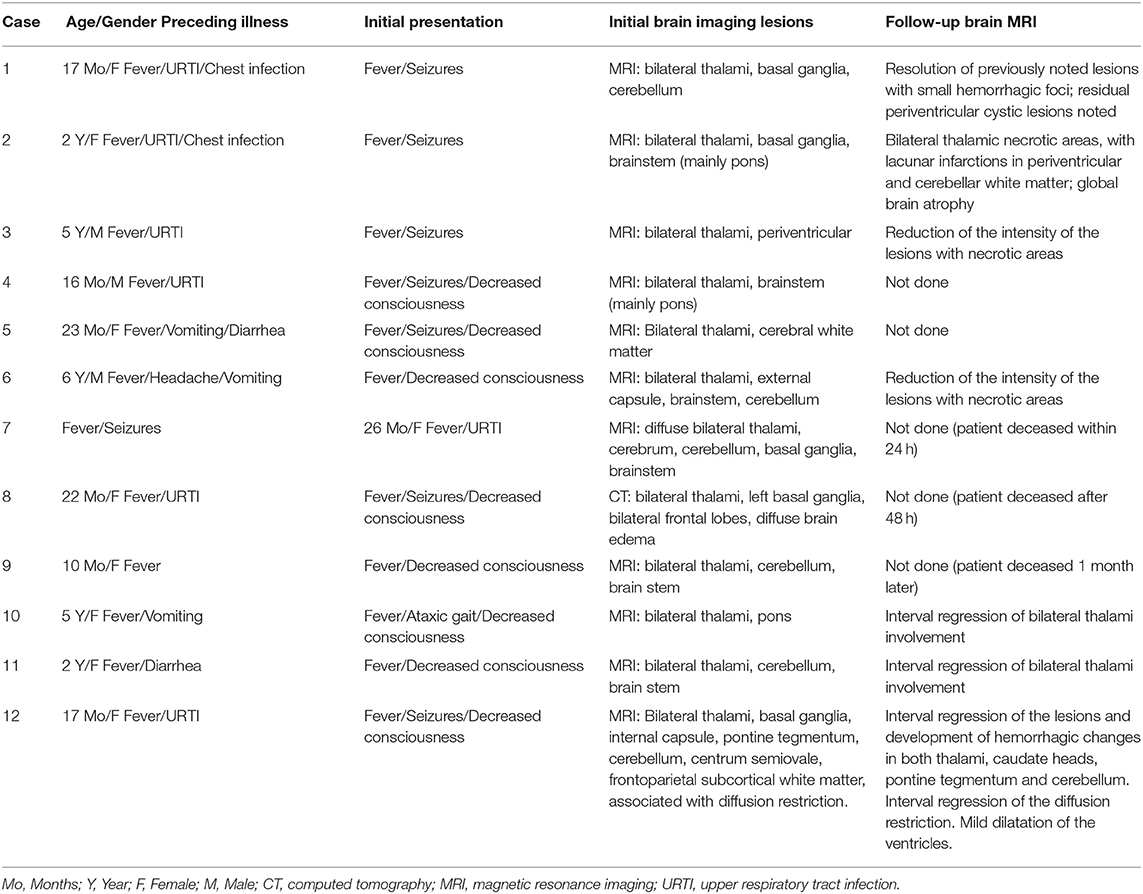

A total of 14 patients with ANEC were identified; two patients were excluded due to the inability to meet the ANEC radiological criteria. Patients' ages ranged from 10 months to 6 years (mean 30.92 months, median 22 months, standard deviation 20.63). Nine patients (75%) were female. All patients presented with preceding febrile illness in the form of upper respiratory tract infection (URTI) symptoms, or gastrointestinal symptoms in the form of vomiting or diarrhea, and altered level of consciousness. Seizures were the initial presentation in eight cases (66.7%). Brain imaging was carried out using Axial, Sagittal, and Coronal T1,T2, FLAIR, diffusion, and susceptibility weighted images which showed characteristic high signal intensity on axial T2 and FLAIR with variable degree of involvement of both thalami in all cases. Diffusion restriction was also seen, while the susceptibility sequence showed dark signal intensity with blooming, indicating hemorrhagic changes. Out of 12 patients, five (41.7%) had brainstem involvement. Follow up brain MRIs were done 2–3 months after the initial presentation, which showed signs of improvement on 33.3%, and 66.7% (n = 8) showed no signs of improvement. The clinical and radiological presentations are summarized in Tables 1, 2. Figures 1–4 show brain MRIs for selected patients.

Figure 1. Brain MRI. Axial T2 (A), FLAIR (B), diffusion (C,D), and susceptibility (E) weighted images. There are swelling and abnormal high signal intensity of both thalami (A,B) with diffusion restriction (C,D) and dark signal intensity with blooming (E).